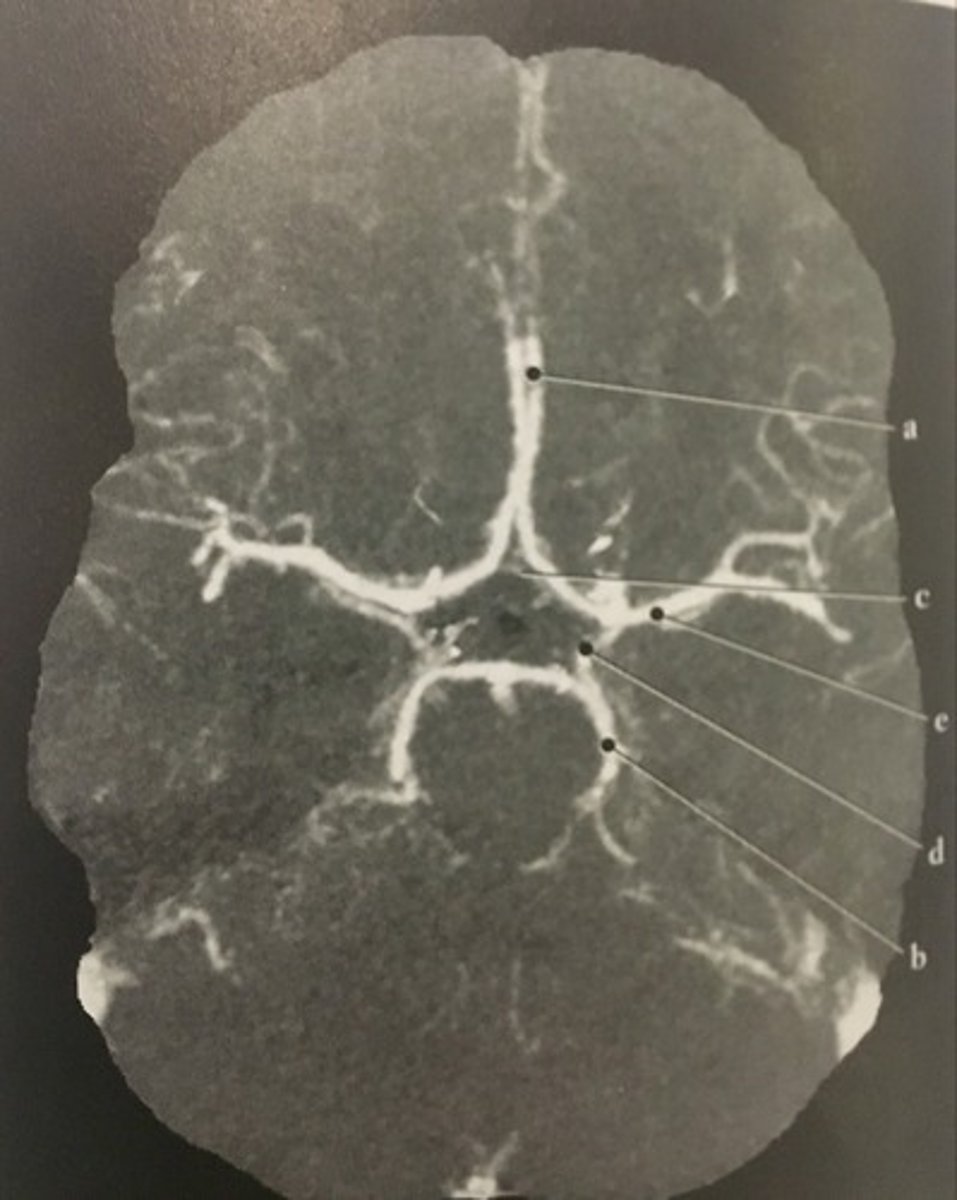

Stomach

Number 1 corresponds to which of the following?

<p>Number 1 corresponds to which of the following?</p>

13

New cards

Soft Tissue

What algorithm was used in this image?

<p>What algorithm was used in this image?</p>

14